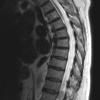

NEOPLASMS (METASTASES)